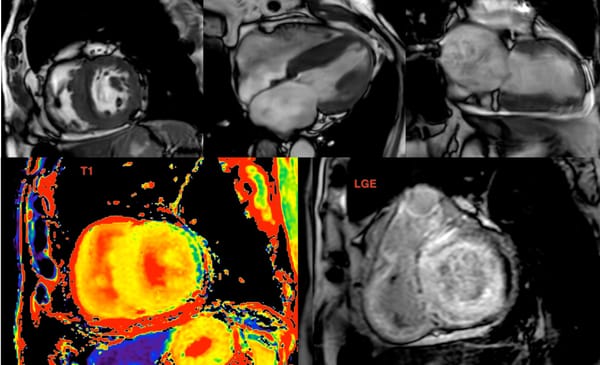

Amyloidosis

Cardiac amyloidosis